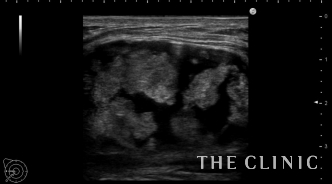

エコーでは、右胸に3cmの混合性のしこりを認めます。

他にも数mmのオイルシストを認めました。